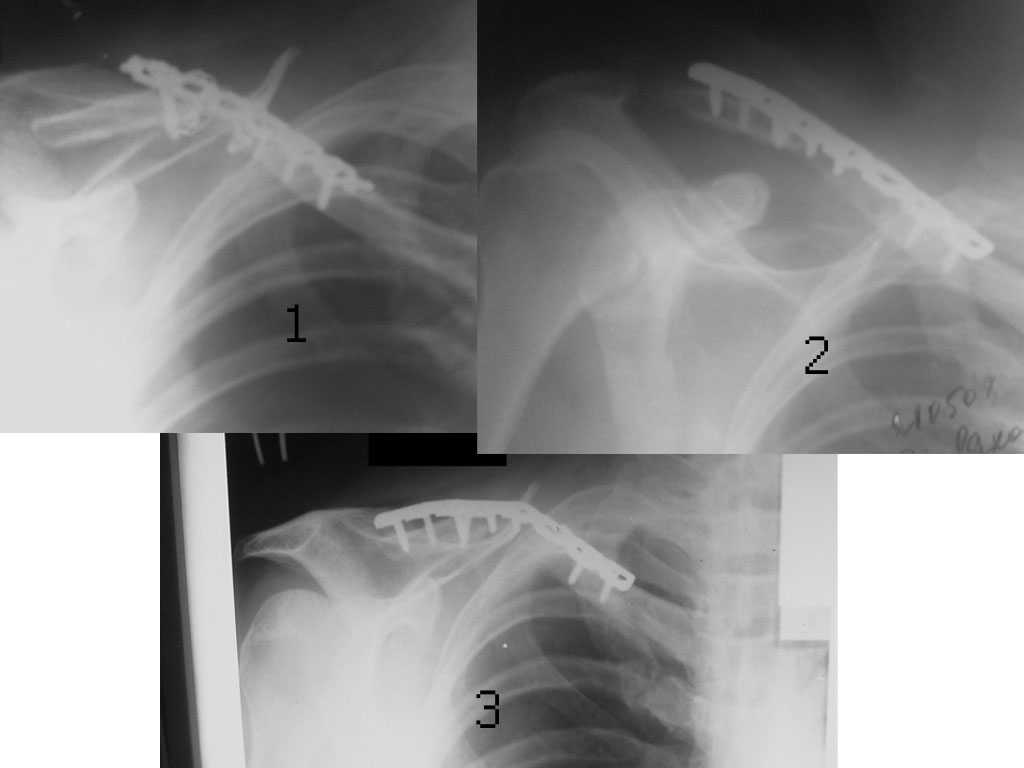

Уважаемые коллеги. Помогите с тактикой дольнейшего лечения несросшегося перелома ключицы. В отделение поступил больной, оперированный 2 мес. назад по поводу оскольчатого перелома средней трети правой ключицы. Перелом несросшийся, фиксатор несостоятелен, имеется смещение, угроза перфорации кожи. Рис. 1 Намми произведен реостеосинтез ключицы пластиной с угловой стабильностью, с замещением деффета диафиза ключицы костным аутотрансплантатом. Рис. 2 Через 5 мес. трансплантат рассосался, повторное смещение, несостоятельность импланта. Рис. 3Ваше мнение,что делать?